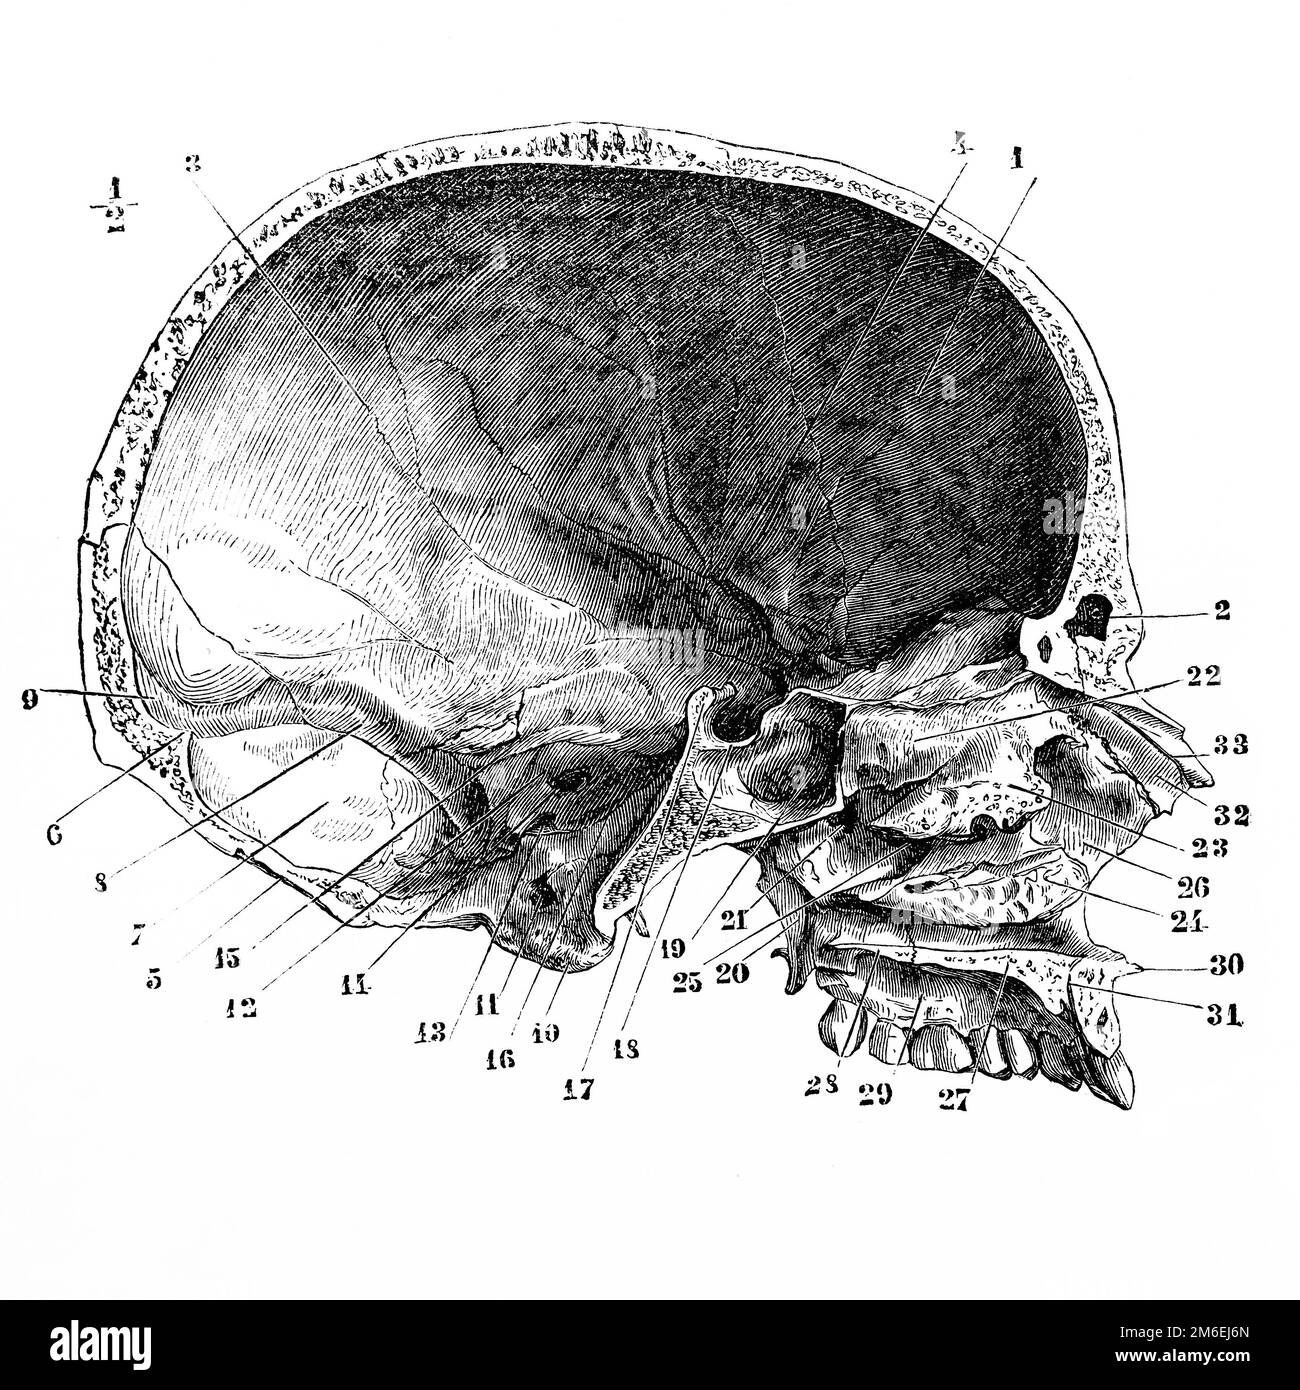

medicine, anatomy, cerebric / cranium, human cranium, side view, wood engraving, 19th century, 19th century, graphic, graphics, skull, death's head, skulls, death's heads, cranial bone, medicine, medicines, historic, historical, people, Additional-Rights-Clearences-Not Available Stock Photohttps://www.alamy.com/image-license-details/?v=1https://www.alamy.com/medicine-anatomy-cerebric-cranium-human-cranium-side-view-wood-engraving-image60149251.html

medicine, anatomy, cerebric / cranium, human cranium, side view, wood engraving, 19th century, 19th century, graphic, graphics, skull, death's head, skulls, death's heads, cranial bone, medicine, medicines, historic, historical, people, Additional-Rights-Clearences-Not Available Stock Photohttps://www.alamy.com/image-license-details/?v=1https://www.alamy.com/medicine-anatomy-cerebric-cranium-human-cranium-side-view-wood-engraving-image60149251.htmlRMDDT0YF–medicine, anatomy, cerebric / cranium, human cranium, side view, wood engraving, 19th century, 19th century, graphic, graphics, skull, death's head, skulls, death's heads, cranial bone, medicine, medicines, historic, historical, people, Additional-Rights-Clearences-Not Available

Median and anteroposterior section of the skull and face. Antique illustration from a medical book. 1889. Stock Photohttps://www.alamy.com/image-license-details/?v=1https://www.alamy.com/median-and-anteroposterior-section-of-the-skull-and-face-antique-illustration-from-a-medical-book-1889-image503110237.html

Median and anteroposterior section of the skull and face. Antique illustration from a medical book. 1889. Stock Photohttps://www.alamy.com/image-license-details/?v=1https://www.alamy.com/median-and-anteroposterior-section-of-the-skull-and-face-antique-illustration-from-a-medical-book-1889-image503110237.htmlRF2M6EJ6N–Median and anteroposterior section of the skull and face. Antique illustration from a medical book. 1889.